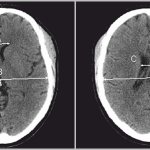

Следует подумать о пункции желудочков при менингите, который не отвечает клинически или микробиологически на проведение антибактериальной терапии из-за вентрикулита, особенно при наличии обструкции между желудочками головного мозга и между желудочками и спинномозговым каналом.